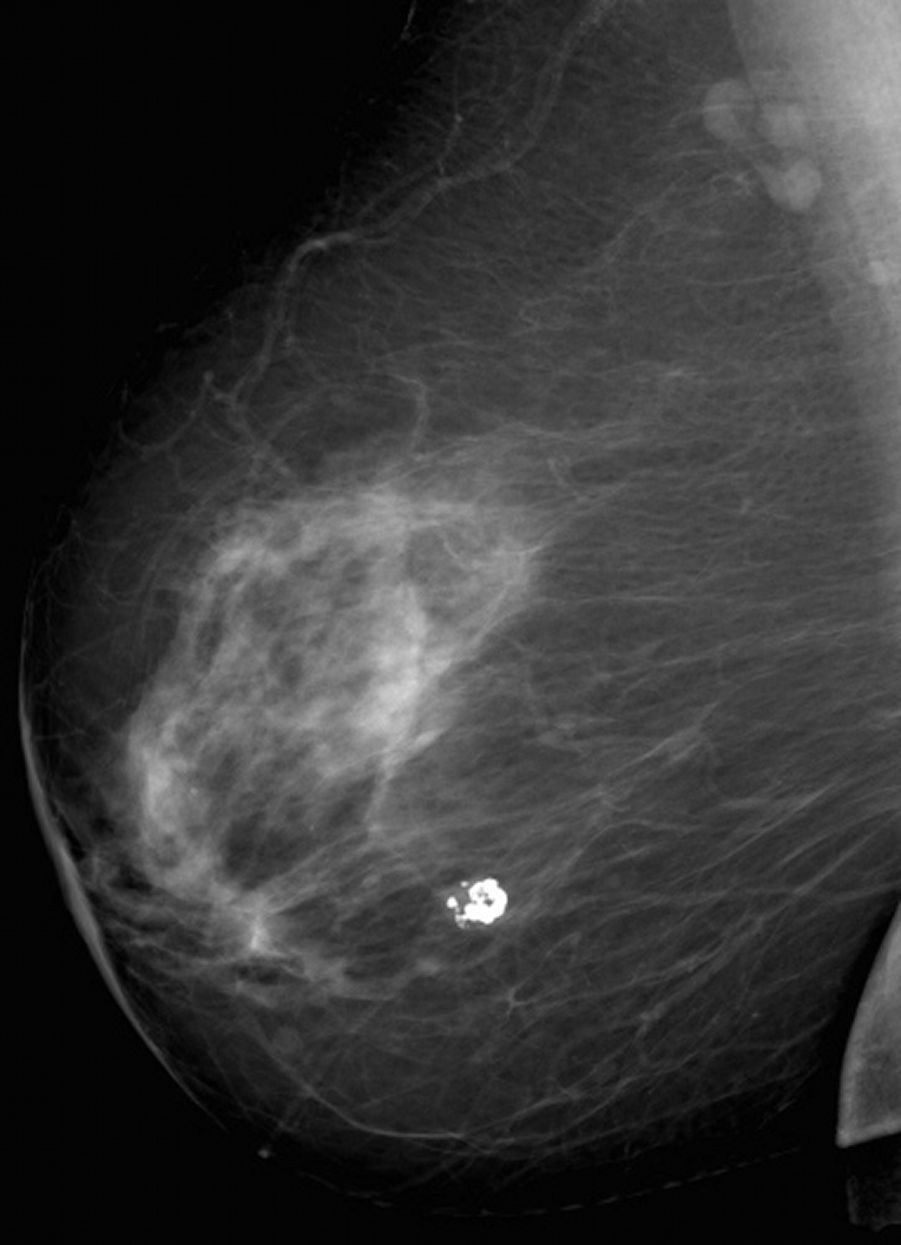

Фиброаденома молочной железы - доброкачественное образование, которое часто встречается у женщин. Оно может быть обнаружено при помощи различных методов диагностики, включая маммографию. Ниже представлены фотографии, помогающие понять, как выглядит данное заболевание.

Маммография и ее роль в диагностике фиброаденомы молочной железы

Маммография - это рентгенологическое исследование молочных желез. Оно позволяет выявить различные изменения в тканях, включая фиброаденому. На маммограммах можно увидеть структурные особенности опухоли и отследить ее динамику во времени.